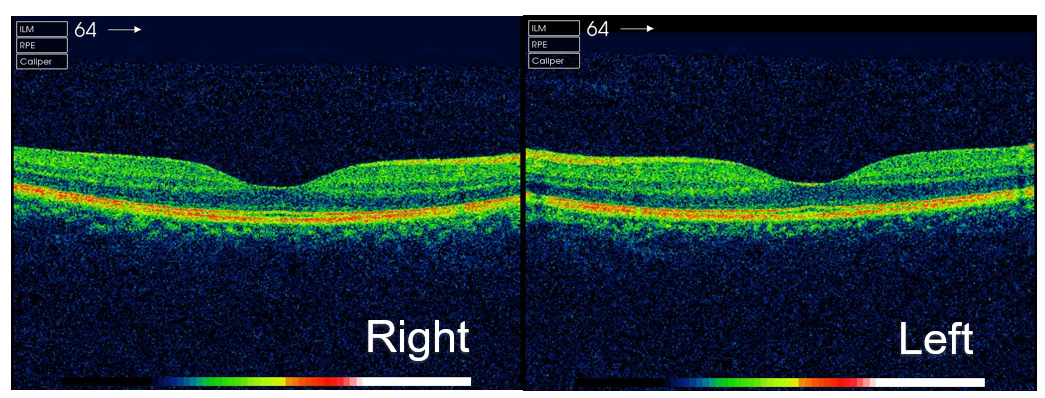

The appearance of ocular symptoms this time, accompanied by arthritis and skin lesions led to a preliminary diagnosis of Blau syndrome for her. Since she was older and could cooperate well with the examination, we conducted a further fluorescein fundus angiography (FFA) and indocyanine green angiography (ICG) for her which showed retinal vascular leakage in the nasal, inferior, and temporal retina of her right eye and inferior of the left, as well as hyper fluorescence in both optic discs (Figure 4). No obvious abnormality was found in optical coherence tomography of macula (Figure 5). Topical dexamethasone and compound tropicamide eye drops were used and controlled the inflammation. In the two years we observed, no serious ocular complications such as cataract or retinal detachment occurred.

Figure 5: OCT shows macula is normal in both eyes.